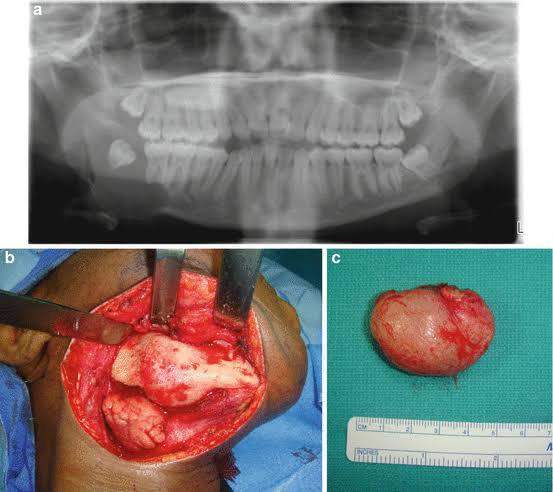

Surgical method for complete cyst removal, minimizing recurrence.

- Purpose: Enucleation is a surgical method used to treat cysts. It involves the complete removal of the cystic capsule, reducing the risk of recurrence.

- Technique: During enucleation, a window is created in the cystic roof, followed by aspiration and evacuation of cystic contents. The cystic lumen is then packed with a wetted ribbon gauze to stabilize the base and reduce the chances of cyst perforation.

- Advantages: Enucleation ensures in toto removal of cysts, minimizing the risk of recurrence. Modifications may be proposed to enhance the procedure.

- Clinical Application: Enucleation is commonly used for treating odontogenic cysts and other benign oral and maxillofacial pathologies.

Surgical removal of jaw tumors, preserving function and aesthetics.

- Purpose: Jaw tumor excision is a surgical procedure to remove tumors affecting the jaw. These tumors can originate from the jaw itself or spread from the mouth or oral cavity. The primary goal is complete tumor removal while preserving function and aesthetics.

- Procedure: During surgery, the surgeon removes the tumor, which may involve taking out nearby teeth, tissue, and parts of the jawbone. The excised tissue is sent to the lab for examination. A pathologist provides a diagnosis during the procedure, allowing immediate action based on the findings.

- Clinical Application: Jaw tumor excision is essential for both benign and malignant tumors. Benign tumors, such as ameloblastomas and central giant cell granulomas, can still cause significant swelling and tooth displacement. Malignant tumors require prompt treatment to prevent spread to other body parts.

- Benefits: Excision ensures accurate diagnosis, reduces pain, and minimizes the risk of recurrence. Reconstruction techniques, such as using bone from the fibula, help restore jaw function and appearance.